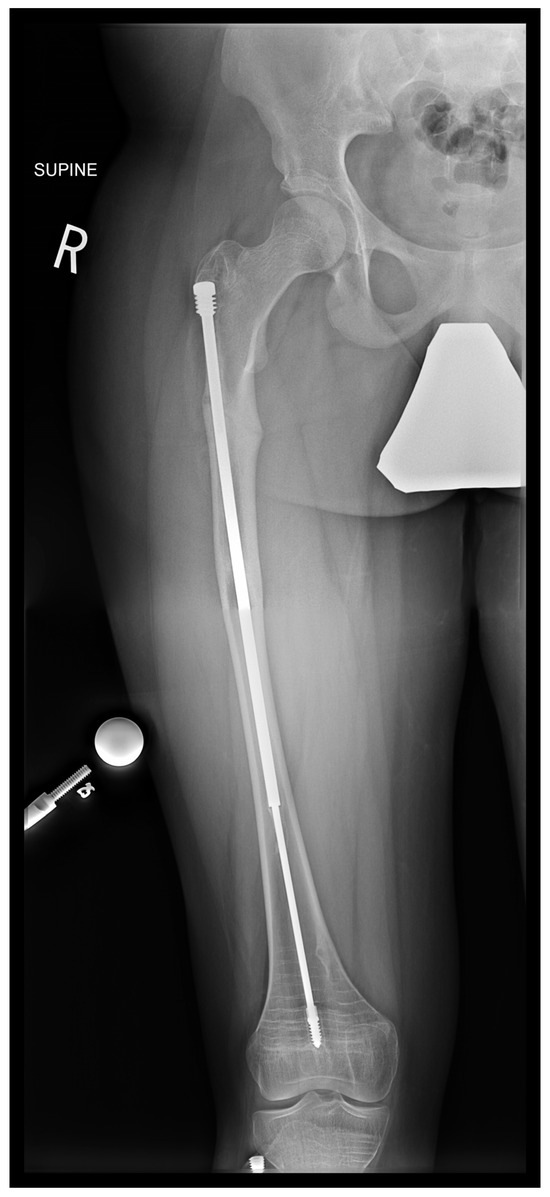

In the second case presented in this paper, a 15-year-old boy diagnosed with OI type IV, who was previously operated on 12 years ago with bilateral FD rods, presented to his regular clinic visit with pain over the left greater trochanter. This patient was ambulating without any braces or aids and was functioning very well. He did not sustain any fractures since the FD rod insertion, and full ROM of his hips was maintained. X-ray showed a completely disengaged FD rod on the left side, where the female component migrated distally and laterally across the lateral cortex. The protruding proximal part of the female component was the site of the pain and tenderness (Figure 10A). On the right side, the FD rod was almost disengaged, and a mild deformity was present anterolaterally. The X-ray demonstrates that the intramedullary canal is too narrow to accommodate an adult-sized nail. As the patient had almost reached skeletal maturity, it was decided not to use another telescoping rod but instead to use a non-telescoping SLIM nail. Because the distal male component of the existing FD rod was situated deep into the canal, making its retrieval problematic, it was decided pre-operatively to leave it in situ and insert the new rod beside it. The female component on the left side needed to be removed, and a solid SLIM rod was inserted to protect the bone (Figure 10B). Revision to a non-telescoping rod was considered for the right side as well; however, surveillance was opted for as the patient was approaching skeletal maturity. In this case, the indication for use of the SLIM nail is a near skeletally mature patient, therefore, not requiring a telescoping nail. However, the intramedullary canal was too narrow to accommodate a larger solid nail.

Figure 10.

(A)—Pre-operative X-ray. (B)—Post-revision X-ray showing installed SLIM nail in the left femur.